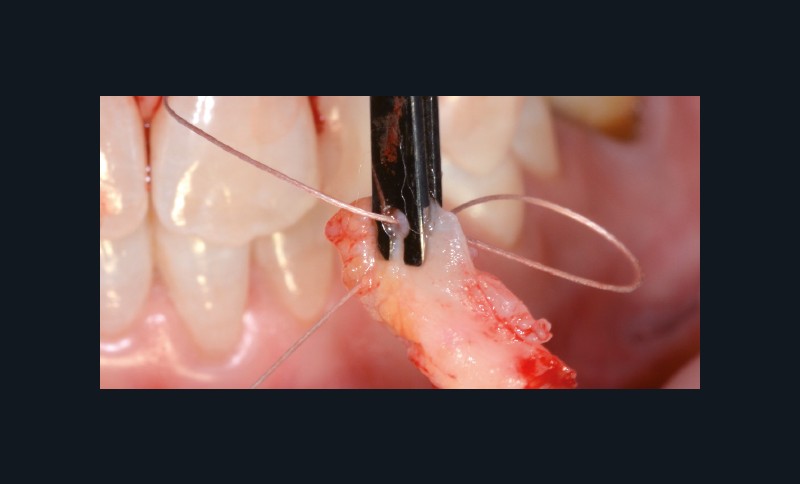

bibli/4.11.jpg_;_;_bibli/4.21.jpgLes points de contacts unis vont permettre se soutenir les sutures qui en feront le tour pour tracter le greffon coronairement.

bibli/3.1.11.jpgUn second fil est passé dans le greffon à son autre extrémité.

bibli/3.1.21.jpgLe second fil est passé dans le tunnel mésial.

bibli/3.1.31.jpgBien vérifier le sens et la parfaite mise à plat du greffon.

bibli/3.2.11.jpgPousser le greffon tout en tractant avec les fils.

bibli/3.2.21.jpgLe greffon est en place, les fils permettent de contrôler sa position dans le sens horizontal.

bibli/3.2.31.jpgDe l’extérieur à l’intérieur, passer dans le greffon et dans la papille pour émerger en palatin.

bibli/3.3.11.jpgRevenir sous le point de contact, en faire le tour pour repasser dessous et suturer au petit chef.

bibli/3.3.21.jpgAvec ces deux sutures suspendues, le greffon est plaqué et tracté vers le collet. Les sutures résorbables distales et mésiales peuvent servir à stabiliser horizontalement.

bibli/2.3.jpgDeux fils sont préalablement montés sur le greffon dans son sens horizontal.

bibli/3.1.jpgLes aiguilles passent les tunnels et le greffon est plaqué horizontalement.

bibli/3.2.jpgLes sutures suspendues vont plaquer le greffon verticalement et le tracter vers la ligne du collet.

bibli/2.3.jpgDeux fils sont préalablement montés sur le greffon dans son sens horizontal.

bibli/3.1.jpgLes aiguilles passent les tunnels et le greffon est plaqué horizontalement.

bibli/3.2.jpgLes sutures suspendues vont plaquer le greffon verticalement et le tracter vers la ligne du collet.